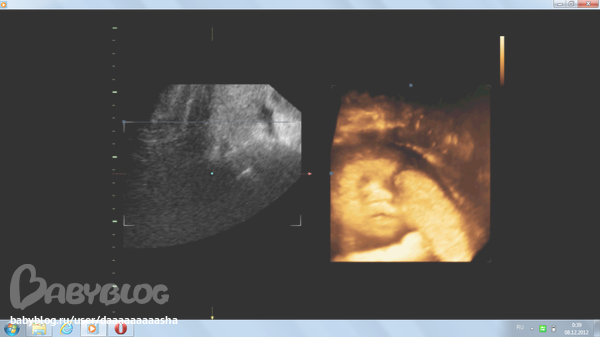

ну и вот пару наших фото... мало что понятно , но по правой стороне видно наш ротик сперва открытый, потом закрытый=))) и ручка трет глазик)